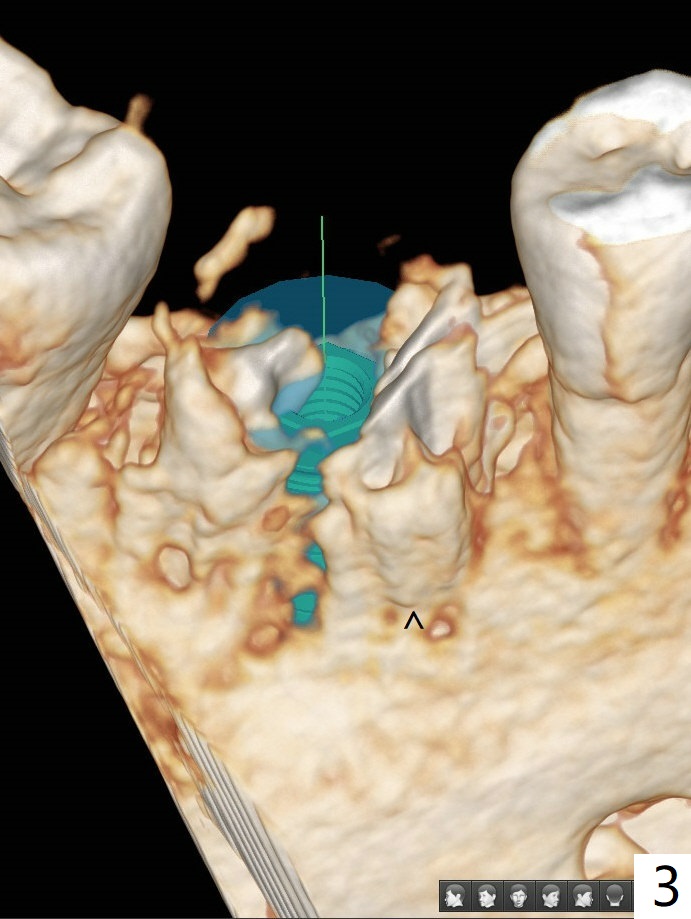

The tooth #30 of a 47-year-old woman has lower buccal crest (Fig.1-3 ^). To prevent post-extraction buccal plate collapse, closed socket shield (Fig.6,8-10 *) will be conducted in the mesial (Fig.1,4-6) and distal (Fig.2,7-10) roots. To decrease vibration, the buccal edge of the roots will be trimmed first (Fig.5,6 a) before root section (Fig.6 b).